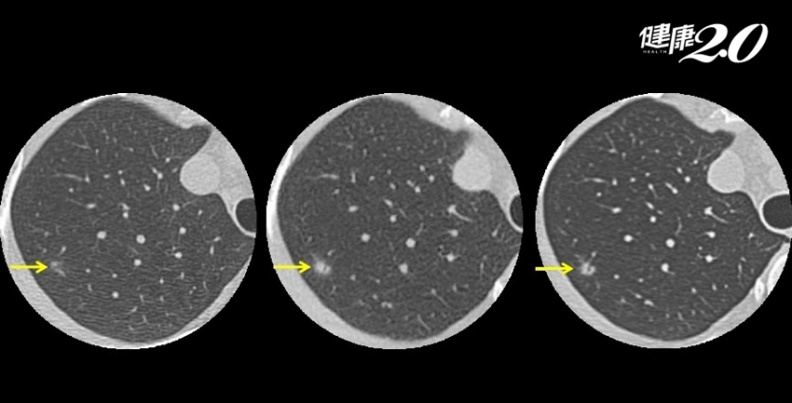

病灶於追蹤期間的變化:在影像上第一次發現病灶時,大部分無法立即判斷它是屬於良性或惡性的結節,可比對間隔幾個月的影像。假設結節是感染發炎引起,通常在觀察期間,一般建議3個月以上,再次以斷層掃瞄追蹤,會逐漸縮小甚至消失,便可判定當初是肺部發炎;若在觀察期間逐漸變大或產生型態的變化,就是異常現象,有必要進一步處理。

▲此個案在觀察期間,結節沒有縮小,逐漸變大且影像密度增加,應當進一步處理。